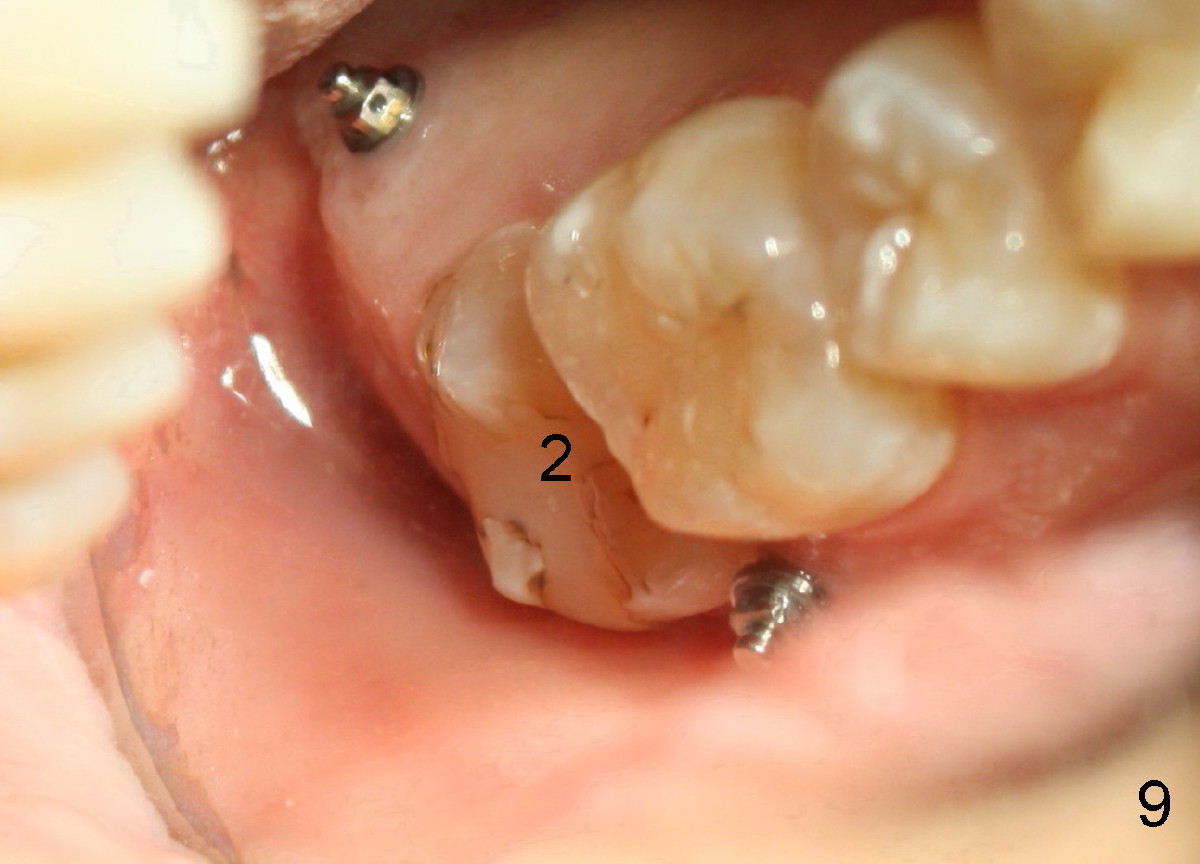

The tooth #31 is uprighted in six months (Fig.8, as compared to Fig.5). The edentulous space increases from 6 mm to 9 mm mesiodistally, which is still not enough. The M-D width of #19 is 12 mm. In fact, the tooth #2 has been intruded substantially (Fig.9. Compare to Fig.3). The possible reason for resistance of distal movement of #31 is an interference from the tooth #3 (Fig.10). A regular implant is placed intentionally in the distal aspect of the edentulous area (Fig.11: I). The next plan is to place temporary crown on the implant once it osteointegrates to raise the occlusion efficiently so that the tooth #31 is free to move distally with retraction of power chain attached to the mini-implant (as shown in Fig.2). The regular implant may be also used as anchorage to push #31 distally. See you later.